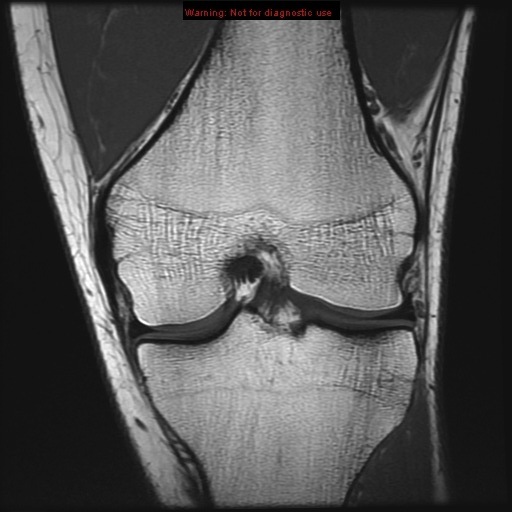

Stanford MSK MRI Atlas

intercondylar notch

sulcus of lateral condyle of femur medial condyle of femur

lateral condyle of femur

lateral epicondyle of femur

posterior cruciate ligament

anterior cruciate ligament